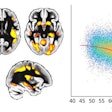

This model, as well as other versions that incorporated additional types of nonimaging data, were assessed on the ADNI dataset, as well as on three independent cohorts of patients. These included 382 subjects in the Australian Imaging, Biomarker, and Lifestyle Flagship Study of Aging (AIBL), 102 participants in the Framingham Heart Study, and 582 subjects in the National Alzheimer's Coordinating Center (NACC).

The researchers found that the best-performing version of the model included consideration of nonimaging variables such as a patient's age, gender, and Mini-Mental State Examination (MMSE) score.

In a head-to-head comparison with a multi-institutional team of 11 practicing neurologists on a randomly selected set of 80 ADNI cases, the model produced an area under the curve (AUC) of 0.996, compared with an average AUC of 0.920 by the neurologists.